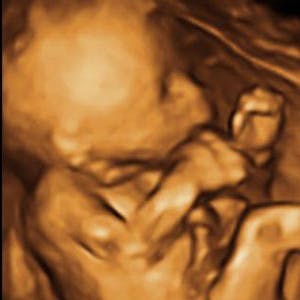

Gravid

Vi gør en dyd ud af at klæde dig godt på både før, under og efter din graviditet. Vi ved, at der kan komme mange spørgsmål til din graviditet, fødsel, amning, din babys udvikling og mange flere emner, derfor har vi samlet guides, tips & tricks samt læsernes egne fortællinger i dette gravid univers.